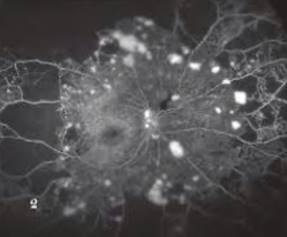

Hình ảnh chụp huỳnh quang võng mạc

Đáy mắt bình thường

Tổn thương đáy mắt do bệnh đái tháo đường